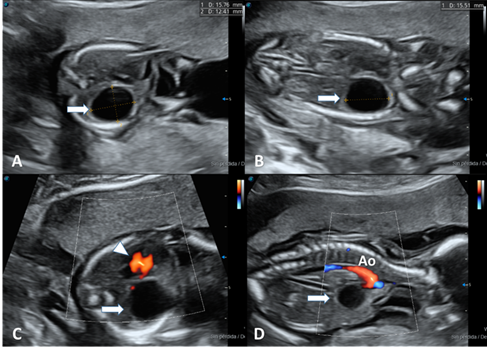

Figure1: obstetric ultrasound showing a unilocular

cystic image (arrow) with echogenic borders in the topography of the right

lung. A and c transverse views. B and d longitudinal view. On color doppler

evaluation, no vascularization is present. Arrow tip: heart, ao: aorta